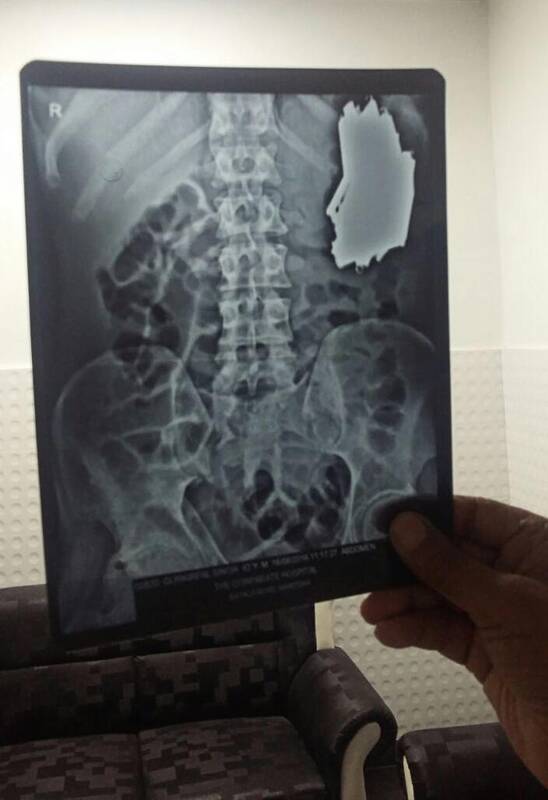

Gydytojai sakė, kad peršvietus pacientui pilvą buvo aptikta iš pradžių augliu palaikyta didelė masė. Įdėmiau ištyrę nuotrauką medikai pamatė, kad vyro pilve yra dešimtys lenktinių peilių metalinėmis ir medinėmis kriaunomis. Kai kurių ilgis, atlenkus geležtę, siekė 18 centimetrų.